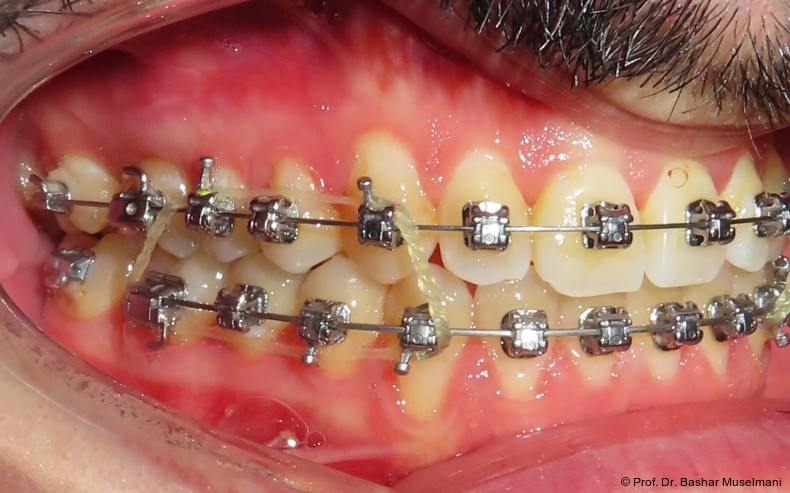

Zur sagittalen Korrektur wurden intermaxilläre Klasse III-Gummizüge eingesetzt.

Zu Beginn der Nivellierungsphase wurden in beiden Kiefern 0.013" CuNiTi-Bögen eingesetzt (Abb. 4a–e).

Bogensequenz und mechanische Umsetzung

Der Bogenwechsel erfolgte in einem standardisierten Intervall von acht Wochen. Die Sequenz war in beiden Kiefern weitgehend identisch und wie folgt aufgebaut:

• 0.013" CuNiTi (OK / UK)

• 0.016" CuNiTi (OK / UK)

• 0.018" CuNiTi (OK / UK)

• 0.014 x 0.0275" CuNiTi (OK / UK)

• 0.016 x 0.0275" Edelstahl (OK)

• 0.018 x 0.0275" CuNiTi (OK / UK)

• Abschlussbogen: 0.018 x 0.0275" TMA (OK/UK)

Diese Sequenz ermöglichte eine schrittweise Ausformung der Zahnbögen, eine kontrollierte Torque-Expression sowie eine präzise Feineinstellung in der Abschlussphase (Abb. 5a–e).